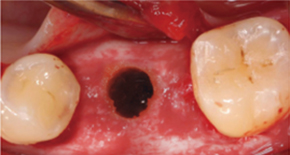

In the case of general cases, without opening the gingiva,

Magic GPS is used to easily and accurately Implants can be placed.

2. No incision, Minimal implant hole

3. Placing MagiCore